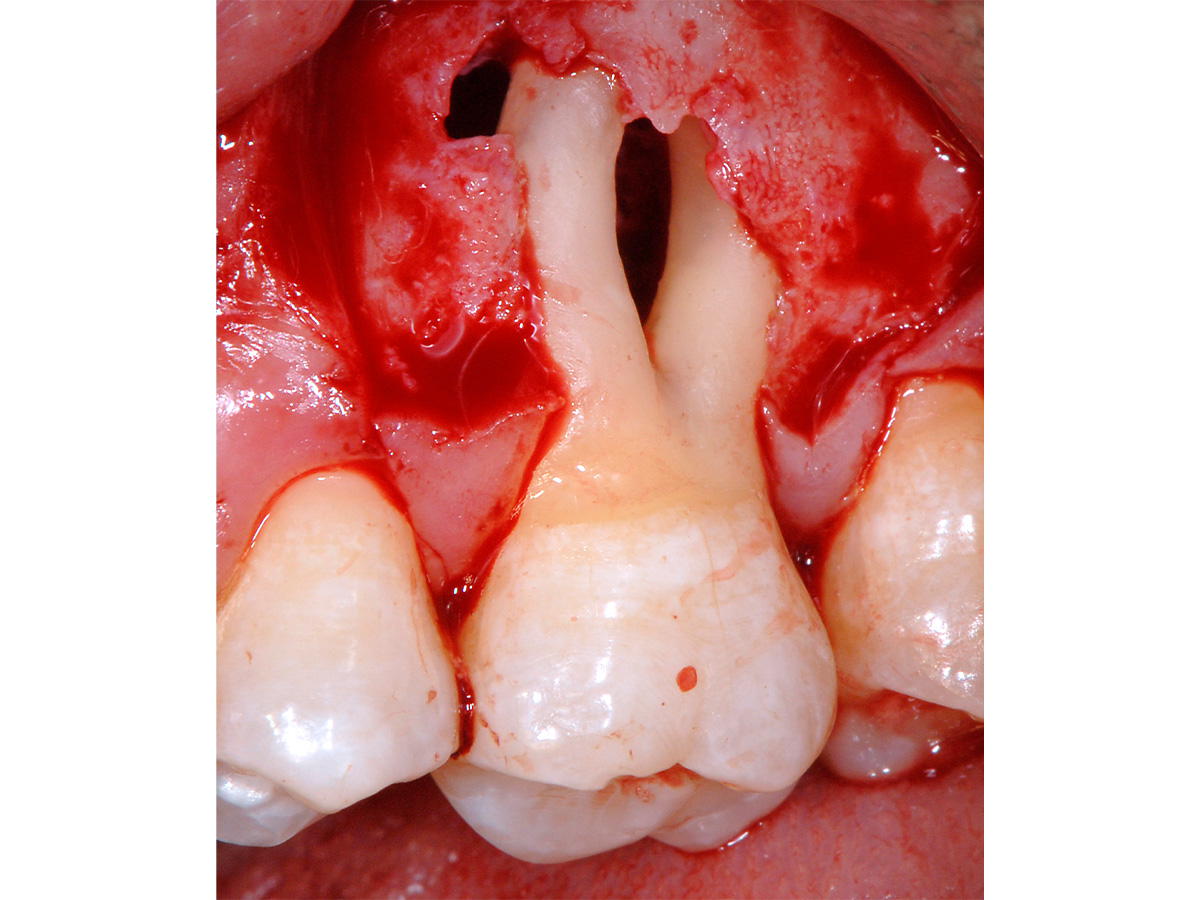

Abbildung 3

Mikrochirurgischer Zugang mit Schonung der interproximalen Bereiche. Vorbereitung dort durch Entepithelisierung zur späteren koronalen Verschiebung der bukkalen Lappenanteile.